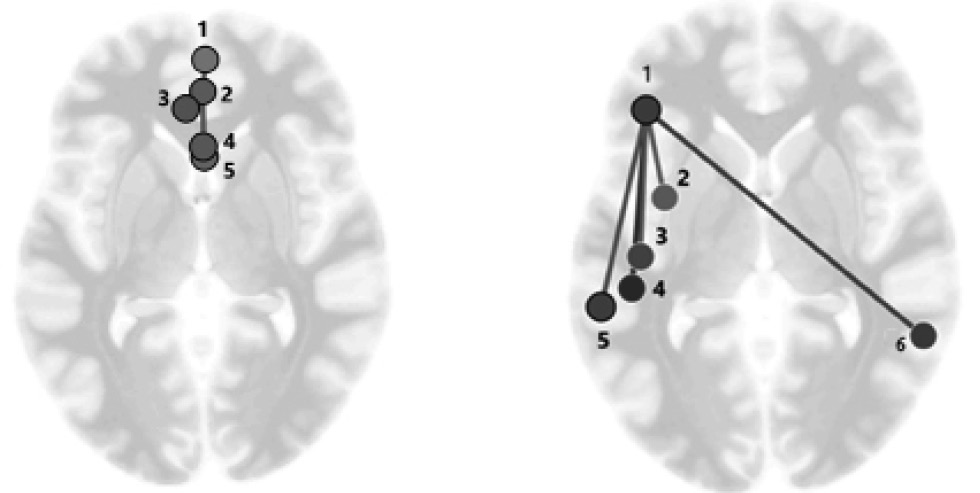

Рис. 2. Статистически значимо преобладающие коннективности в группе с нормальным венозным оттоком по сравнению с группой с низкой скоростью венозного оттока (a) и в группе с низким венозным оттоком по сравнению с группой с нормальным венозным кровообращением (b). Остальные объяснения в тексте; a (1 — Default Mode medial prefrontal cortex (Default Mode MPFC, 2 — Frontal Medial Cortex (MedFC), 3 — Paracingulate Gyrus (PaCiG), 4 — Salience Network anterior cingulate cortex (Salience ACC), 5 — Cingulate Gyrus anterior (AC)); b (1 — Fronto-Parietal NetWork, lateral prefrontal cortex (Fronto- Parietal LPFC, 2 — Insular Cortex (IC), 3 — Heschl’s Gyrus (HG), 4 — Parietal Operculum (PO), 5 — Salience NetWork, supramarginal gyrus (Salience SMG), 6 — Temporooccipital part Middle Temporal Gyrus (toMTG))

Средняя систолическая скорость кровотока по правой и левой ВЯВ в группе с низкой скоростью венозного оттока составляла 21,2 ± 1,1 см/с, а при высокой — почти в два раз больше (41,5 ± 2,4 см/с). При этом количество воспроизведенных слов в тесте Лурия составило 30,1 ± 1,0 слов при низкой скорости кровотока, а во второй группе с более высокой скоростью кровотока — 35 ± 1,3 слов. Теперь рассмотрим организацию нейросетей, преобладающих в группах с хорошей и плохой вербальной памятью. В группе пациентов с хорошей памятью преобладали коннективности, локализованные в лобной области, включая области сетей пассивного режима работы мозга и салиентную сеть. У испытуемых с плохим запоминанием основные коннективности сосредоточены в левом полушарии и связаны с лобно-теменной сетью (рис. 2).

Статистические характеристики коннективностей, представленных на рис. 2, a и b, приведены в таблице. Все выделенные коннективности статистически значимы с учетом FDR.